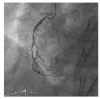

Takotsubo cardiomyopathy (TCM) is usually characterized by transient left ventricular apical ballooning. Due to the clinical symptoms which include chest pain, electrocardiographic changes, and elevated myocardial markers, Takotsubo cardiomyopathy is frequently mimicking ST-elevation myocardial infarction in the absence of a significant coronary artery disease. Otherwise an acute occlusion of the left anterior descending coronary artery can produce a typical Takotsubo contraction pattern. ST-elevation myocardial infarction (STEMI) is frequently associated with emotional stress, but to date no cases of STEMI triggering TCM have been reported. We describe a case of a female patient with inferior ST-elevation myocardial infarction complicated by TCM.